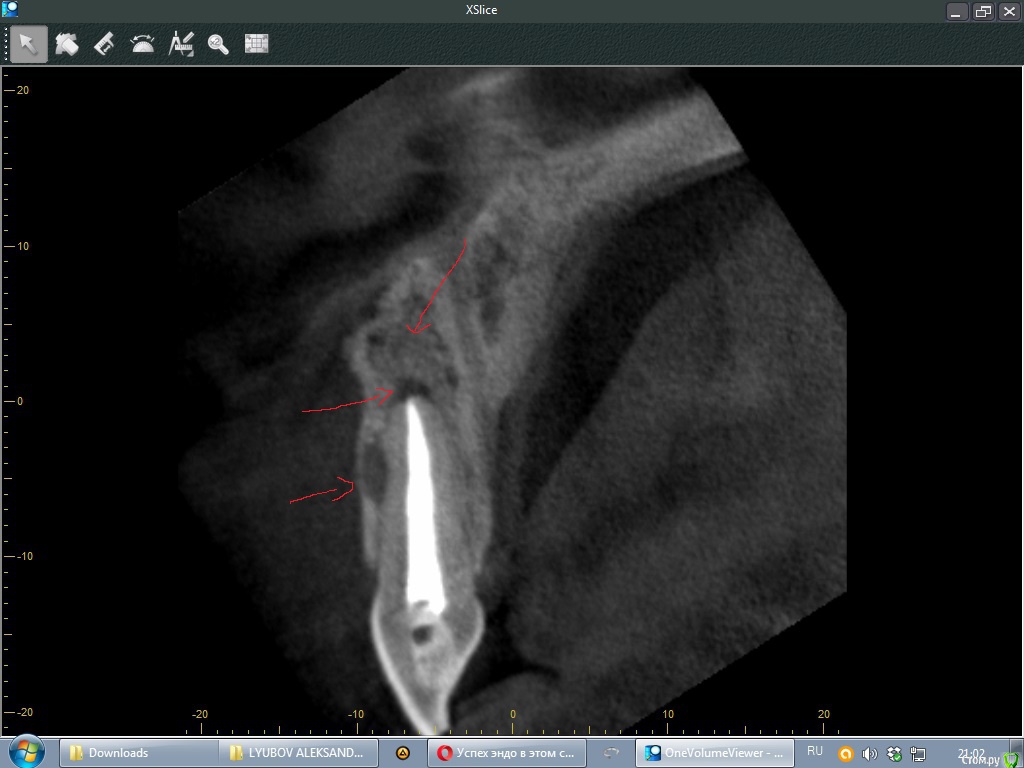

Doctor Vlad Опубликовано 29 августа, 2016 Поделиться Опубликовано 29 августа, 2016 Добрый день, уважаемые доктора!Оцените возможность сохранения 11 зуба с маргинальной и апикальной резорбцией зуба. причину на кт не нашел, но корень тоже поеден. переломов не определил. пломбирован гомогенно! мб перегрузка штифта? зубы 21 и 22 ранее ( 2 года назад по словам) сделана рвк; есть смысл повторной операции? Ссылка на комментарий

Тимур86 Опубликовано 30 августа, 2016 Поделиться Опубликовано 30 августа, 2016 Сдаётся мне трещина там... 4 Ссылка на комментарий

Nazim_NV86 Опубликовано 31 августа, 2016 Поделиться Опубликовано 31 августа, 2016 Сдаётся мне трещина там...после агрессивной обработки протейперами скорее всего ... 1 Ссылка на комментарий

Doctor Vlad Опубликовано 2 сентября, 2016 Автор Поделиться Опубликовано 2 сентября, 2016 после агрессивной обработки протейперами скорее всего ...возможно!какой механизм травмы маргинального периодонта при обработке протейпером(машинный наверно?) перегрев локальный? Ссылка на комментарий